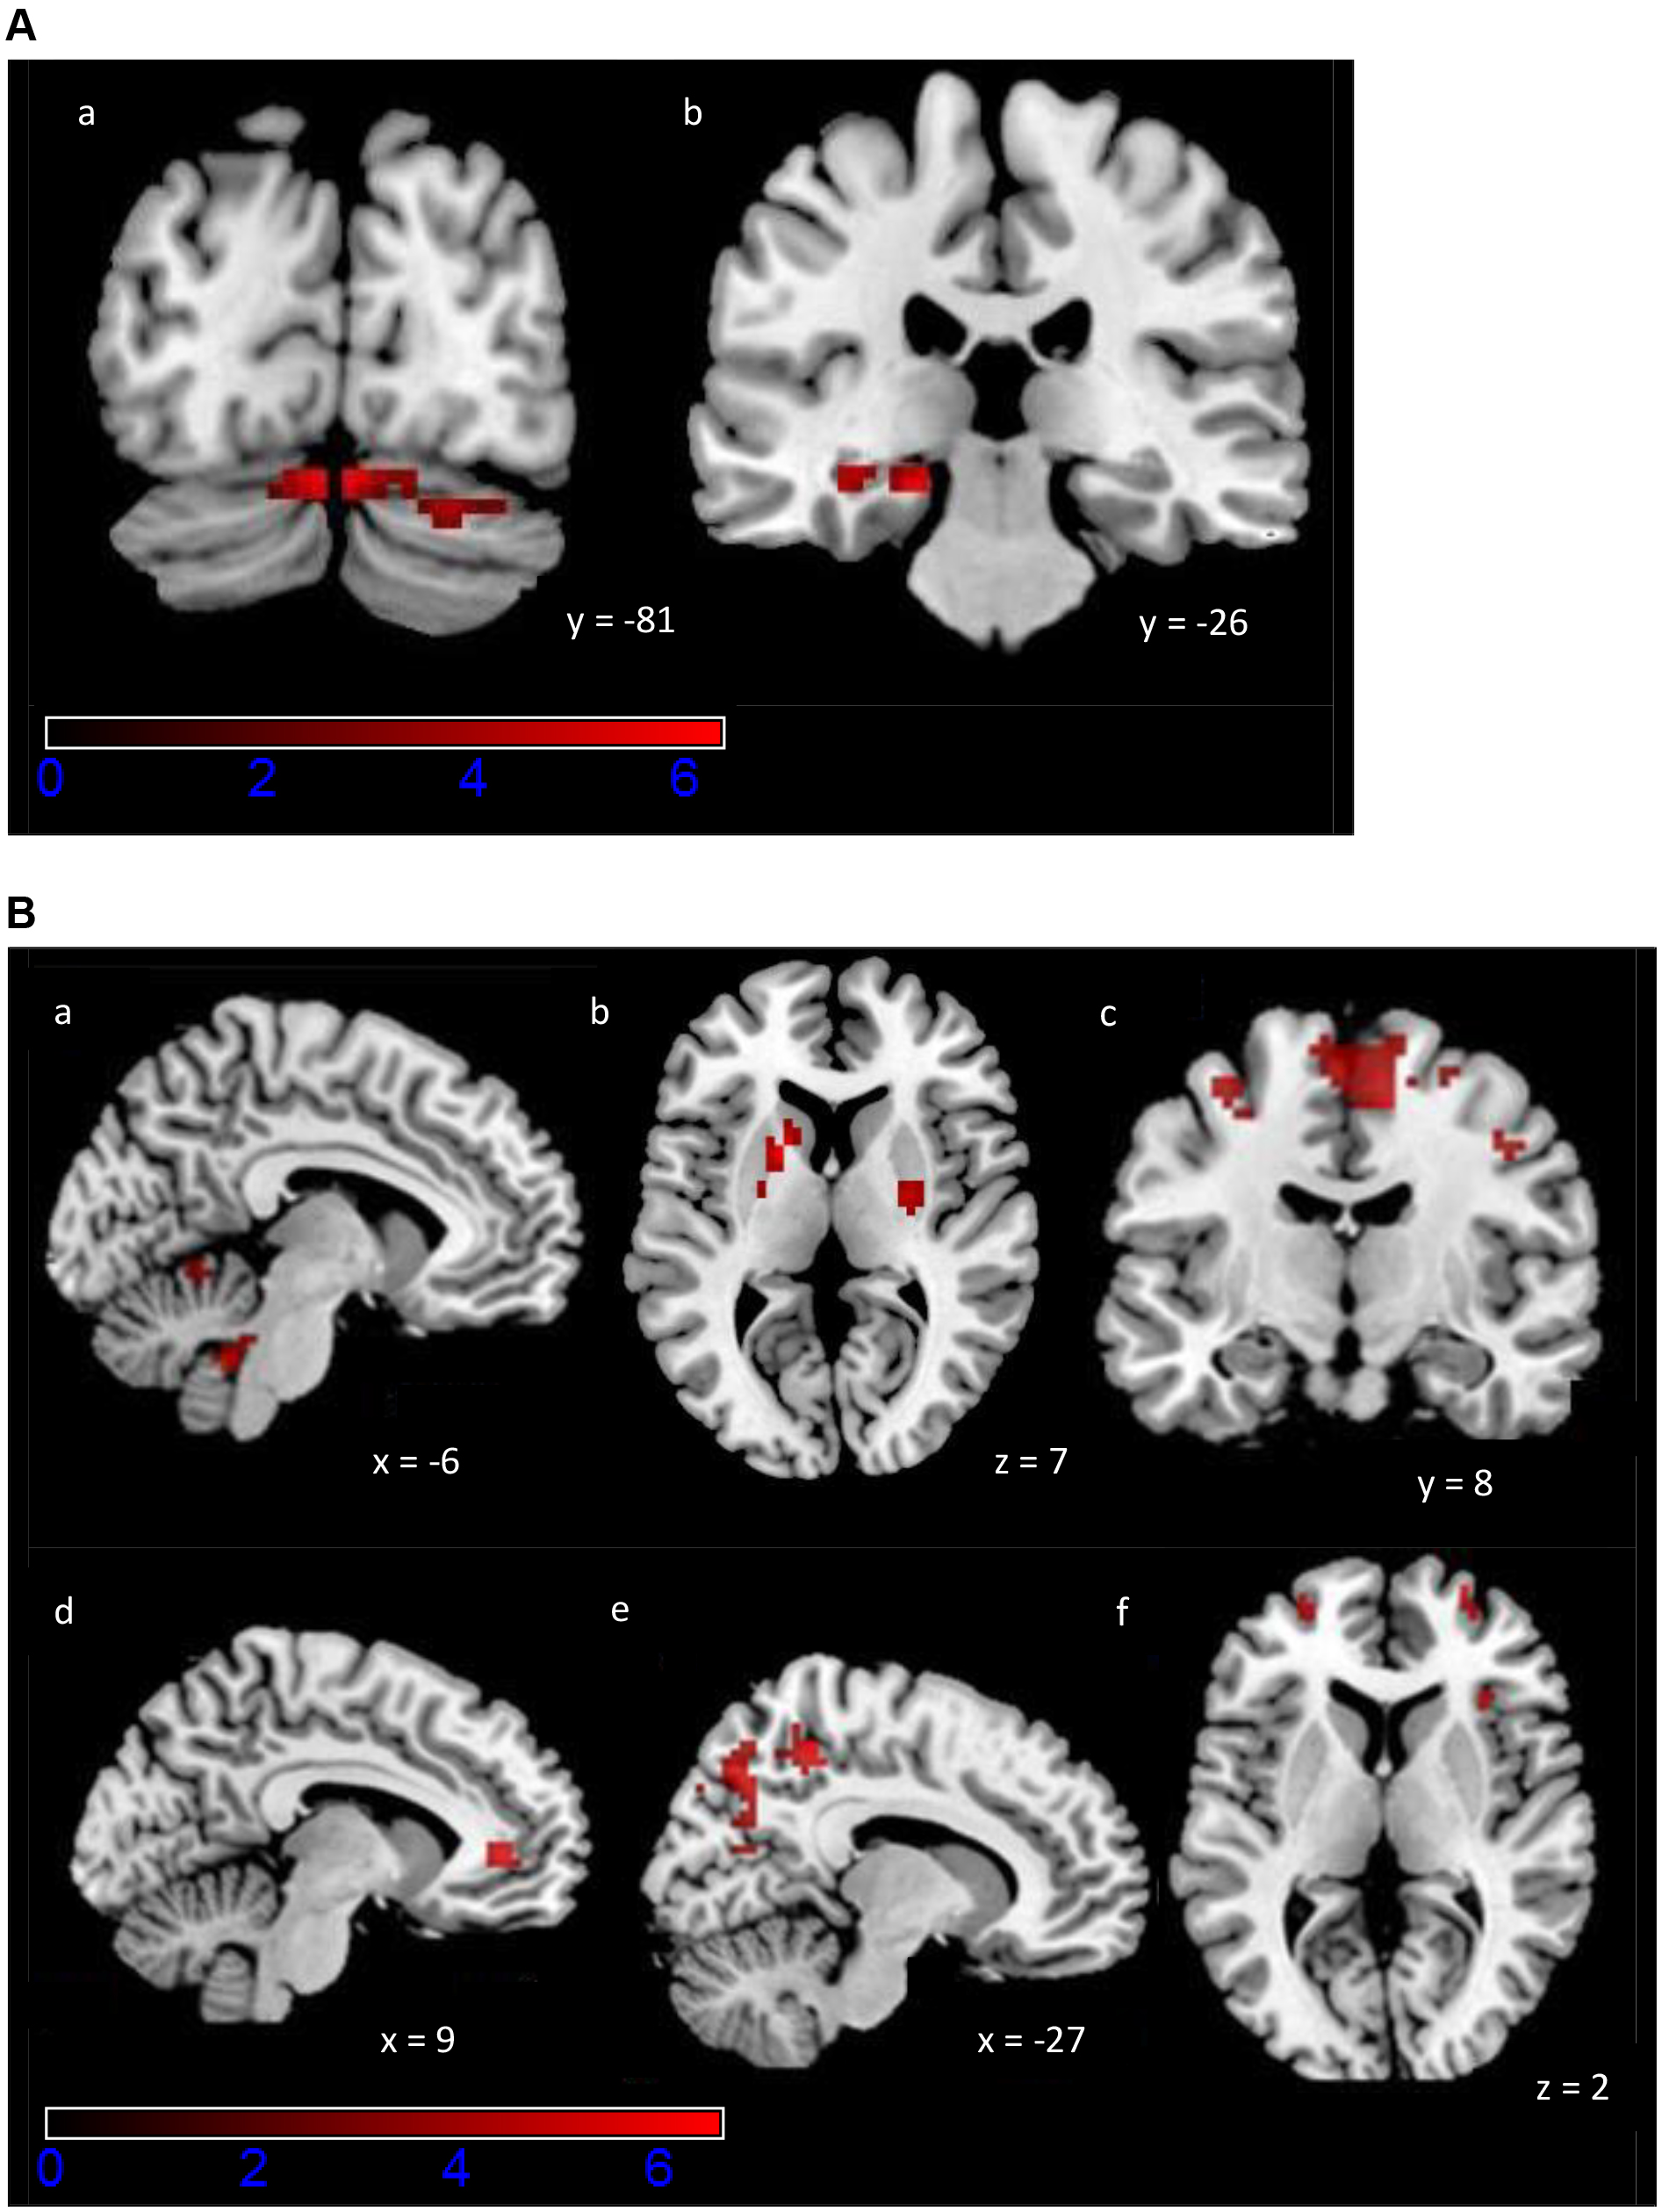

Fig. 3. Activation maps of the exploratory ROI analysis for the PCM task. Colour scale indicates z-scores, ranging from 0 to 6. (A) Increased activity during Early Learning (a) bilaterally in cerebellum, (b) left parahippocampal gyrus and hippocampus. A statistical significance of p

| Late | |||||||

| Cerebellar vermis (10) | 3 | –46 | –34 | 6.56 | 317 | 0.002 | |

| Left pons | –3 | –19 | –22 | 5.17 | |||

| Right thalamus | 6 | –22 | –1 | 4.53 | |||

| Right pons | 3 | –28 | –37 | 3.92 | |||

| Right subthalamic nucleus | 9 | –13 | –10 | 3.53 | |||

| Right precuneus | 12 | –43 | 53 | 5.10 | 185 | 0.019 | |

| Right mid cingulate cortex | 9 | –1 | 41 | 4.56 | |||

| Right SMA | 3 | –22 | 65 | 4.05 | |||

| Left paracentral lobule | –3 | –16 | 68 | 4.04 | |||

Followed by brain regions with increased activity in the Late relative to the Early Learning phase (Late

We then looked for correlations between the LI and the diffusion MRI indices. We applied a statistical significance threshold of p

| Brain region | MNI coordinates | t-value | Cluster size (voxels) | p-value FDR-corrected | |||

| FA negative correlation with LI | |||||||

| Right SMA (WM) | 18 | –20 | 58 | 5.28 | 35 | 0.002 | |

| Right SMA (WM and GM) | 12 | –20 | 60 | 4.83 | |||

| MD negative correlation with LI | |||||||

| Left cerebellum (IV–V) (GM) | –20 | –48 | –22 | 5.30 | 95 | ||

| Left cerebellum (VI) (GM) | –22 | –54 | –20 | 5.19 | |||

| Left middle temporal gyrus (GM) | –48 | –54 | 14 | 5.61 | 33 | 0.038 | |

| Right cerebellum (VI) (GM) | 24 | –72 | –18 | 4.65 | 29 | 0.049 | |

| ODI positive correlation with LI | |||||||

| Right SMA (WM) | 16 | –22 | 58 | 5.25 | 22 | 0.014 | |